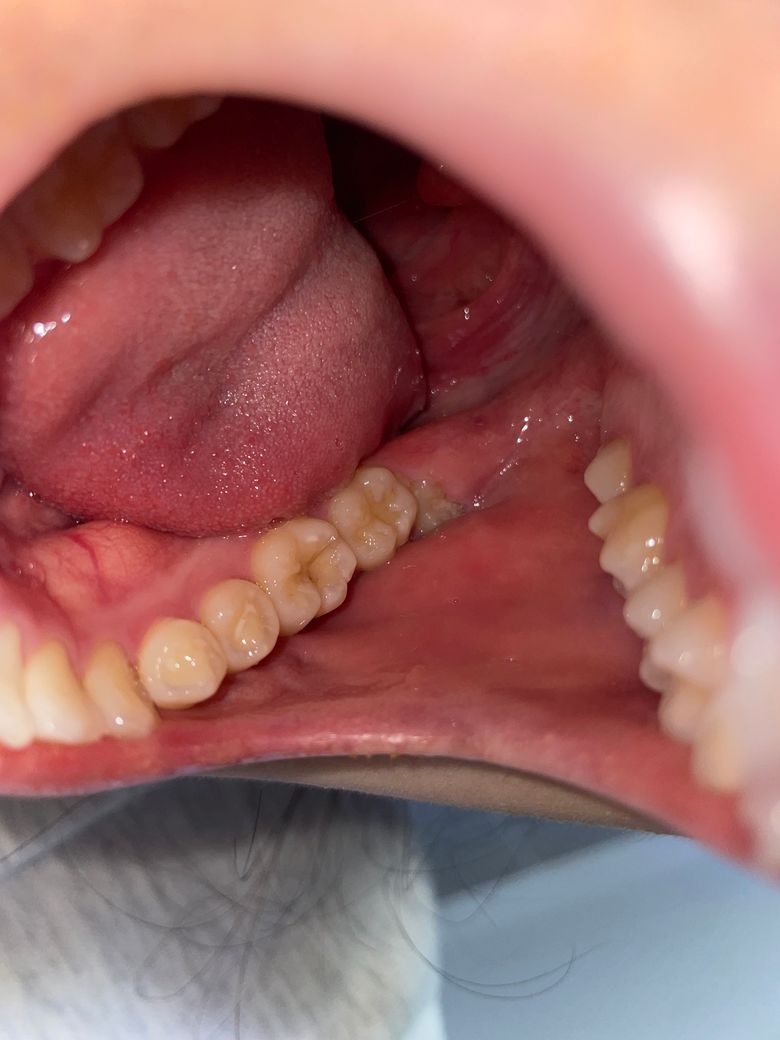

충치일까요?? 구멍은 뭔가요? 치료하려면 많이 아플까요ㅠ

충치일거같긴한데… 구멍도 있는거같아서요ㅠㅠㅠ차가운거 먹었을때만 좀 시려요 ..금데 한 1-2초 후에 바로 괜찮아집니다..!! 근데 제가 치과를 목요일쯤에 갈수있을거같은데 그 사이 더 심해지진 않겠죠 ㅠㅠ? 혹시 이 충치 치료려면 얼마나 아플까요..?ㅠㅠㅠ

어금니에 충치가 보입니다. 따라서 해당 부위의 치료가 필요할 것으로 보이나 현재 차가운것에 시린 증상은 해당 치아로 인한 것인지 다른 치아에도 문제가 있는지는 치과 방문 후 검진을 받아보셔야 합니다. 대부분 충치는 진행속도가 크지 않으므로 단순히 일주일 정도 지나서 치과를 방문하더라도 큰 차이는 없습니다. 물론 가급적이면 빨리 치과를 방문하는 것이 좋습니다.

많이 심해보이지는 않지만 간혹 보기보다 충치가 더 많이 진행된 경우도 종종 있습니다.

충치는 있으실꺼 같긴합니다. 하지만 저기 구멍뚤린건 원래 치아 모양이 그렇게 생긴거에요. 충치 깊이는 엑스레이 사진등을 찍어보시고 판단해야되니 치과에 가셔서 검진을 받아보세요.

첫번째 큰어금니의 작은 충치일 가능성이 있습니다.